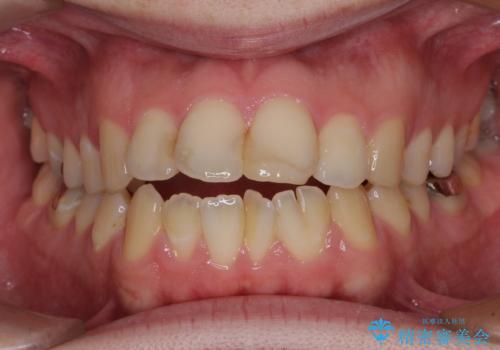

しゃくれて口が閉じられない ワイヤー装置での抜歯矯正

- 口がうまく閉じられないとのことで来院された患者様です。

上下唇をしっかり合わせようとすると、顎先が前方に突出してしまうほど口が閉じにくい状態でした。

口元の突出感を改善するために上下左右の第一小臼歯4本を抜歯し、ワイヤー装置にて矯正治療を行うこととしました。

また、上下前歯は舌の突出癖による開咬となっていたため、舌のトレーニングを徹底するよう指示しました。